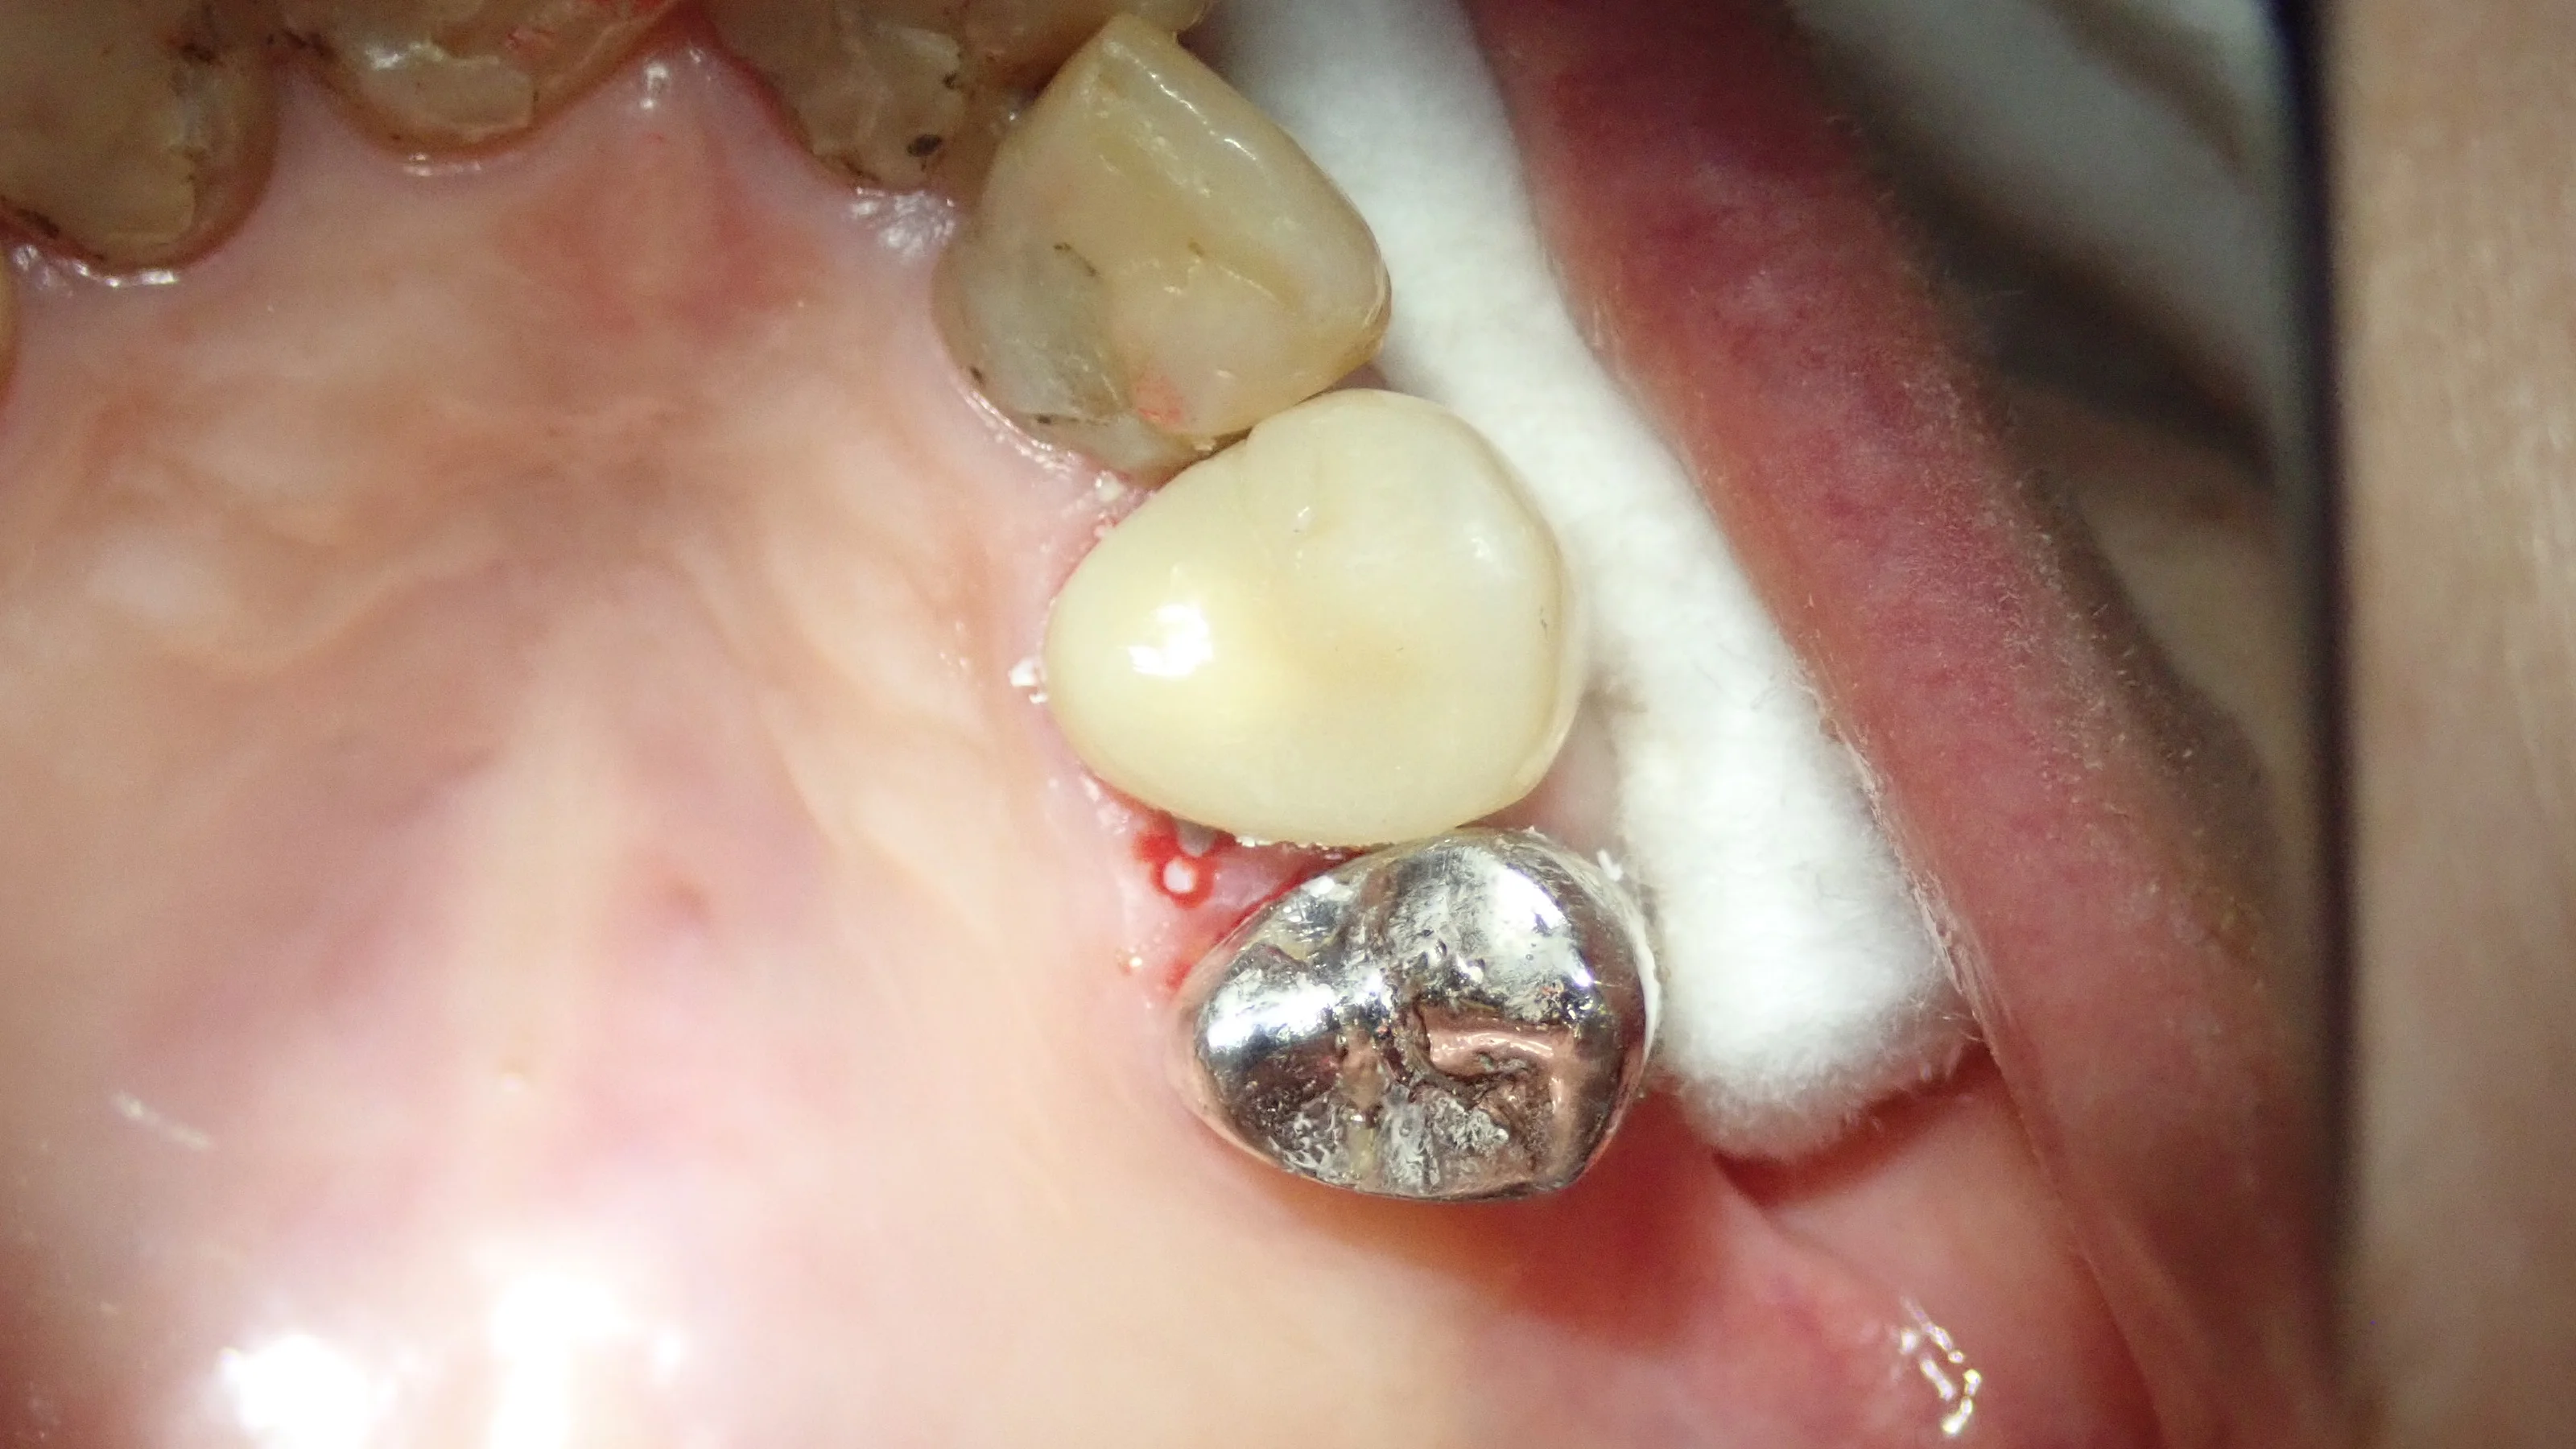

で、Set時の写真です。

横からの図

咬合面(噛む面のことです)の形態が凹凸の無い形状になっていますが、これは技工士さんのエラーというわけではありません。

セラミックであれば、裂溝(咬合面に存在する溝)を付与してもその強度からも特に大きな問題はありませんが・・・

HJCはそうはいきません。下手に裂溝を作成してしまうとそこの強度が落ちるため、割れてしまう危険性があります。

今回は、歯ぎしりを多くされる方でしたので、歯の長さを短くするわけにはいきませんでしたので、裂溝をなくす方向にしました。